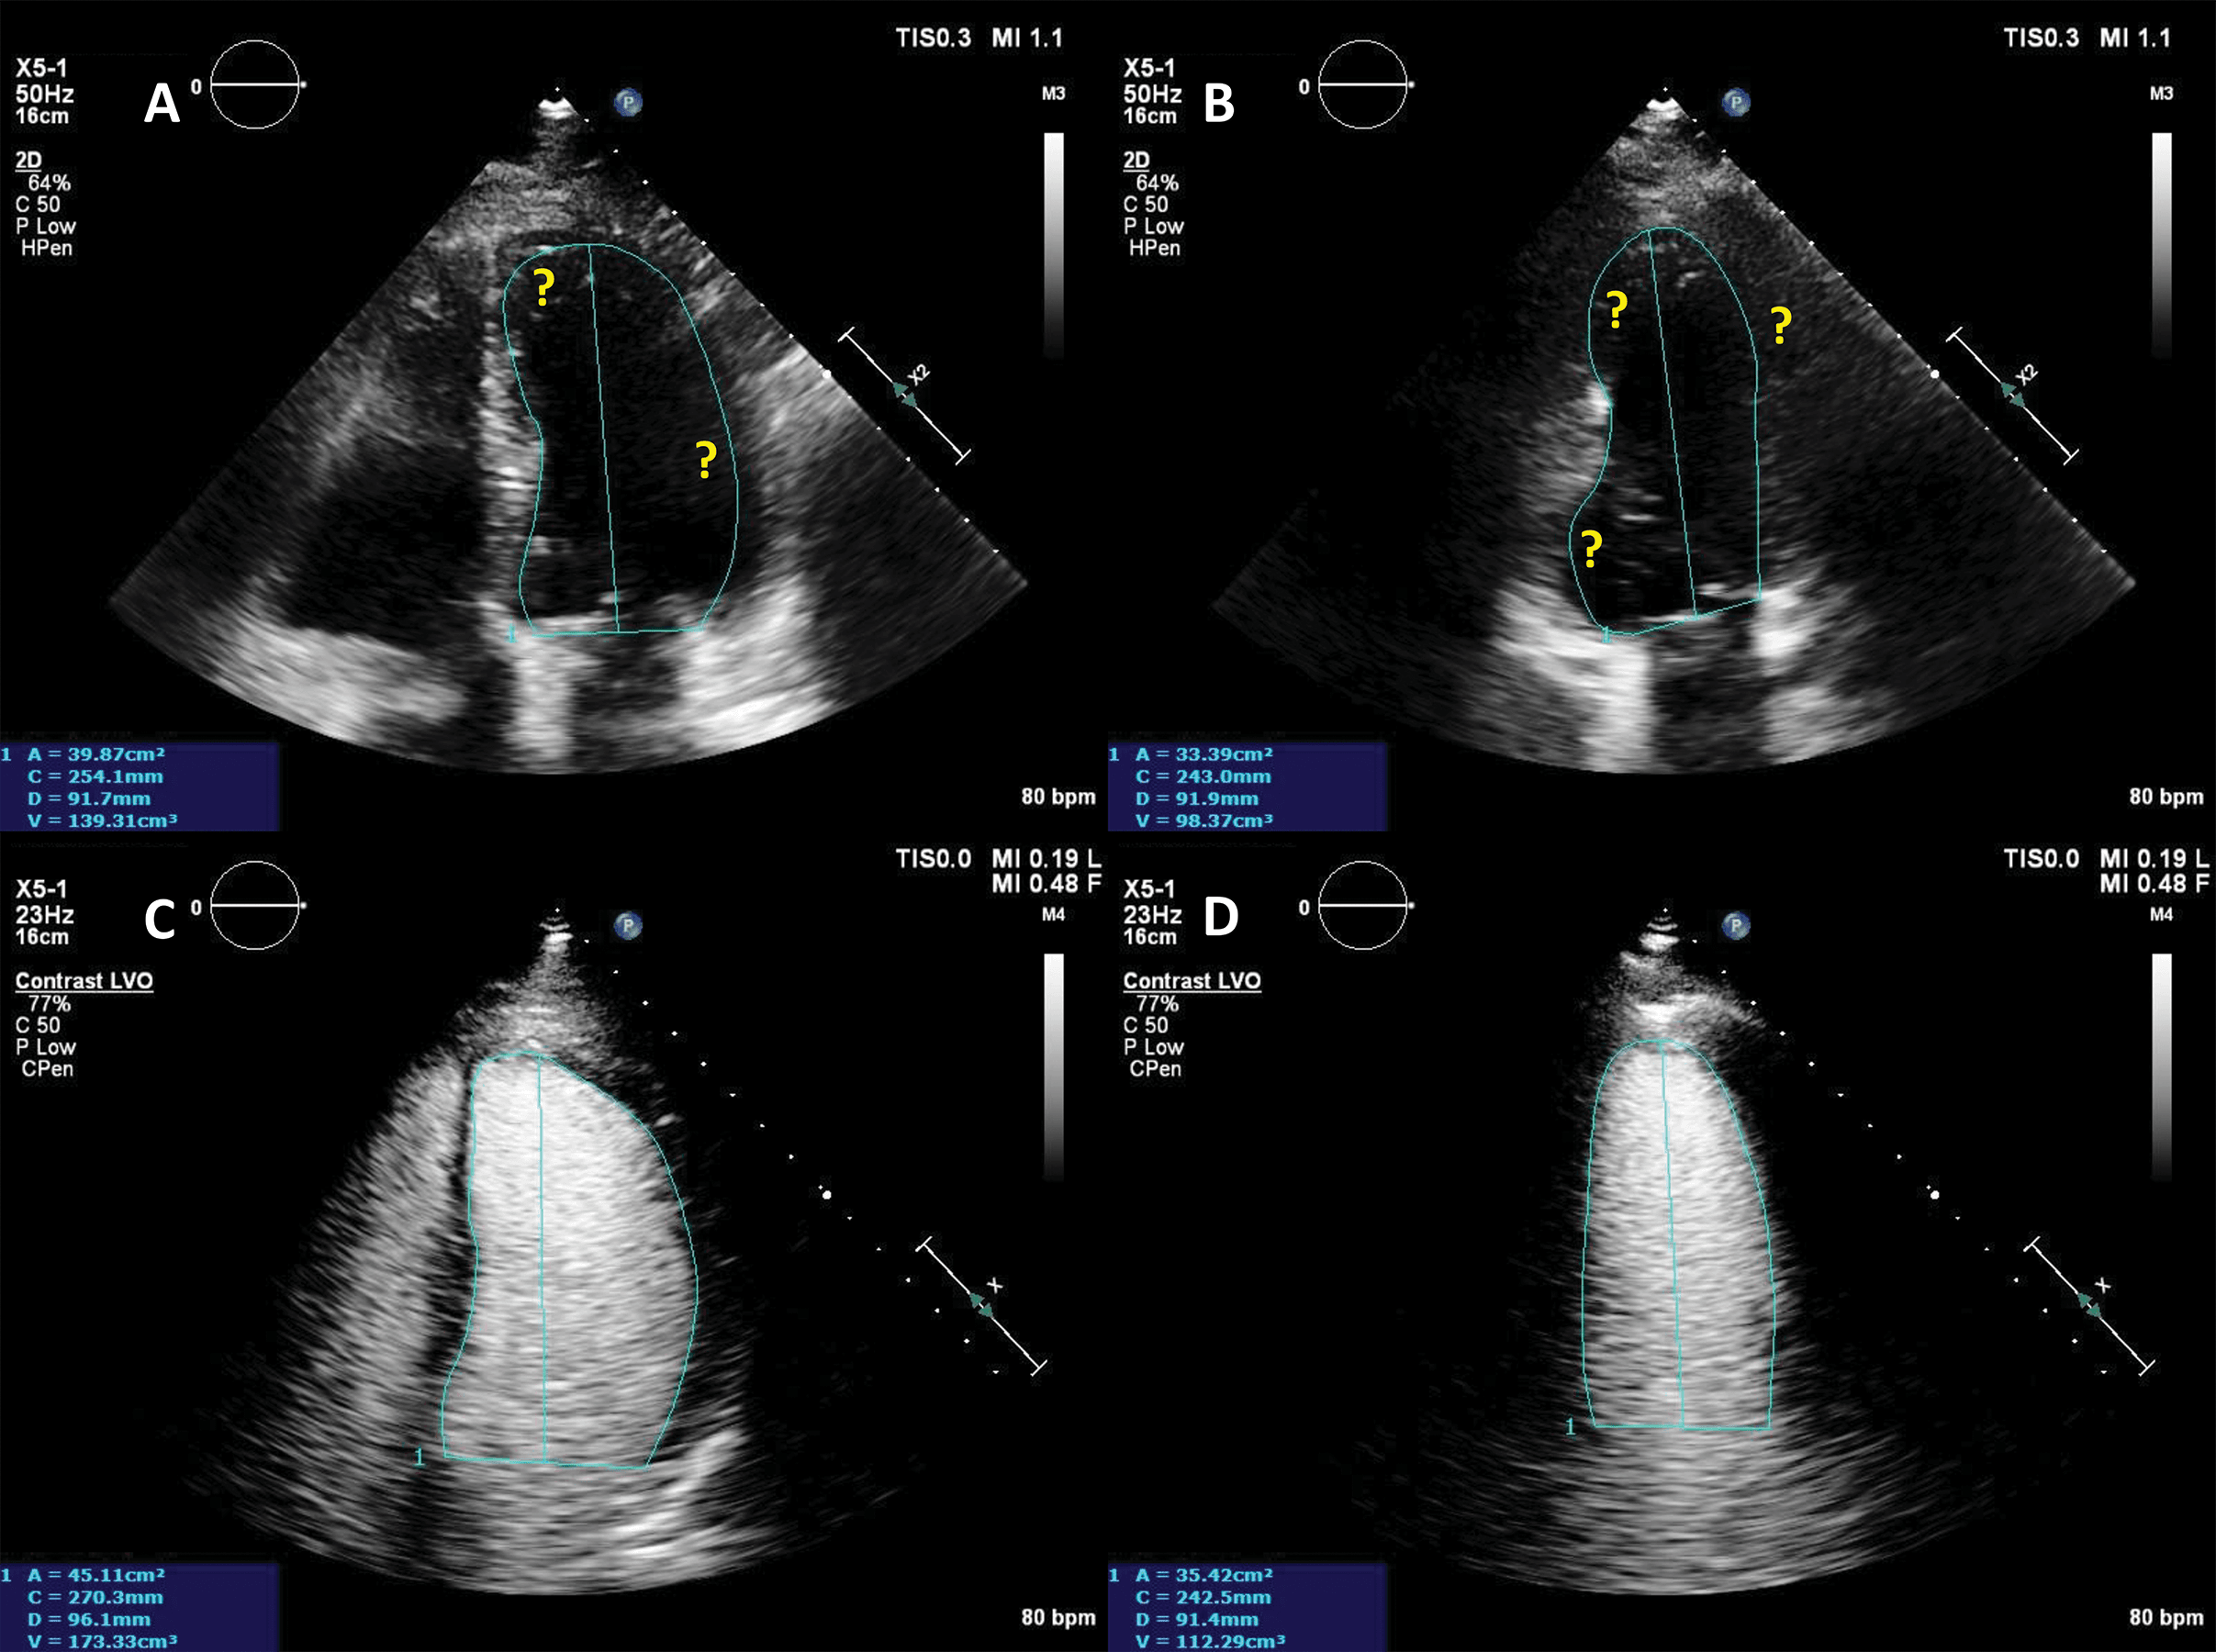

The addition of UEA during stress echocardiography protocols is usually achieved through an LVO application with low-MI harmonic imaging (Fig. 7, Video 6). The result is an increase in the likelihood of a diagnostic test, a better visualization of all myocardial segments, study quality and reader confidence, as compared to invasive or non-invasive reference [40, 41, 42, 43]. The addition of UEA to non-enhanced studies resulted in a better agreement with coronary angiography, even in patients with intermediate coronary lesions [44]. Of course, the use of LVO in stress echo has the largest impact in patients with suboptimal image [45]. Nevertheless, contrast-enhanced ultrasound also improves the wall motion score and detection of regional wall motion abnormalities in patients with adequate image quality [46]. Contrast-enhanced dobutamine stress echocardiography provided adequate risk stratification in patients with increased cardiovascular risk due to obesity or suspected coronary artery disease [47, 48, 49].

Fig. 7.Microbubble enhanced stress echocardiography. Baseline non-enhanced images are recorded in apical 4 and 2 chambers (A,B), demonstrating insufficient delineation of the endocardial borders; With contrast (C,D) the LV contours become clearly visible. Source: personal collection.

In patients with incomplete visualization of at least 2 contiguous segments contrast should be used for stress echocardiography. In patients with adequate image quality, contrast could be used to assess the myocardial perfusion, in addition to wall motion [7, 13].